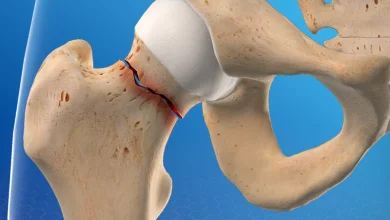

شکستگی لگن در دوران کرونا: ایران شاهد روندی غیرمنتظره در درمان بود

به گزارش پایگاه خبری علمی ریشامگ، با شیوع پاندمی کووید-۱۹ در سراسر جهان، سیستمهای مراقبتهای بهداشتی با چالشهای بیسابقهای روبرو…

هشدار برای بیماران مبتلا به شکستگی لگن با ترومای خفیف: خطر شکستگی مجدد و مرگ در سال اول

به گزارش پایگاه خبری علمی ریشامگ، مطالعه جدیدی که در مجله BMC Geriatrics منتشر شده نشان داد که افراد مبتلا…